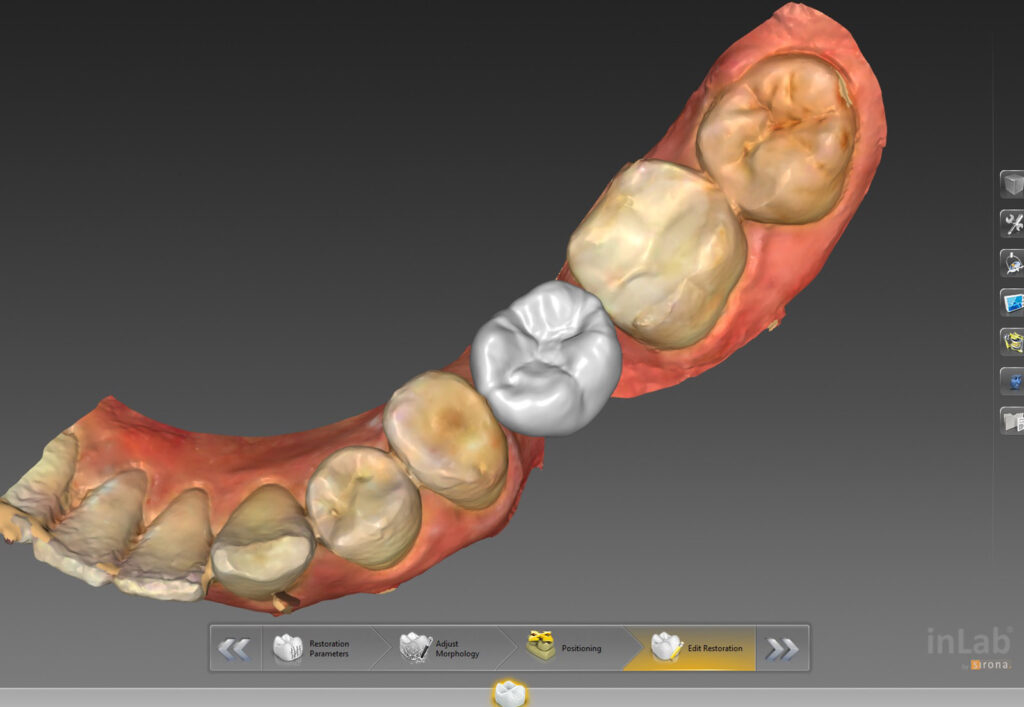

Implant to mała „śruba” wkręcana do kości, zastępująca korzeń zęba. Na takim podłożu zostaje usytuowana korona protetyczna. Zabieg przeprowadzany jest w znieczuleniu miejscowym, jest trwały i bezpieczny. Pozwala odbudować brakujący ząb nawet w trakcie jednej, krótkiej wizyty.

Podczas zabiegów implantacyjnych wykorzystujemy szablony chirurgiczne – komputerowo nawigowana implantologia.

Zadaniem szablonów jest precyzyjne prowadzenie narzędzi chirurgicznych w określonym miejscu i pod określonym kątem. Narzędzia przygotowywane są na podstawie planu przedoperacyjnego. Każdy szablon jest niepowtarzalny i pasuje tylko do jednego pacjenta.